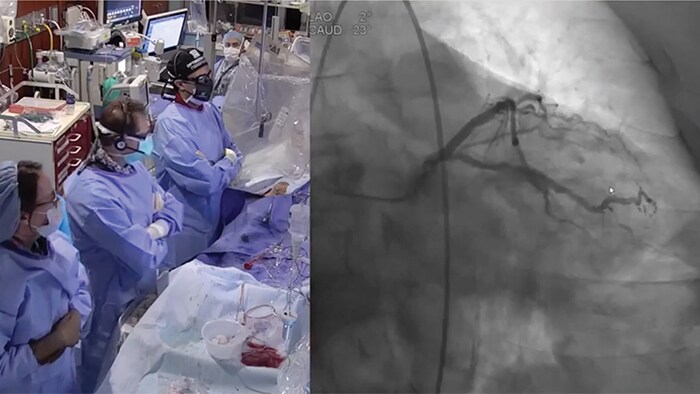

Коронарография с ультранизкой дозой контрастного вещества и ЧКВ с нулевым контрастированием для профилактики контраст-индуцированной нефропатии: пошаговый алгоритм и обзор методики

Новые методы инвазивной визуализации и программное обеспечение для ко-регистрации позволяют выполнять ЧКВ с ограниченным объемом контрастного средства и даже проводить ЧКВ с нулевым контрастированием для снижения риска развития КИ-ОПП для всех пациентов, особенно для пациентов с почечной недостаточностью.

Решения Philips для ЧКВ объединяют неинвазивные методы, а также ВСУЗИ и iFR, требующие меньше контраста для постановки правильного диагноза.